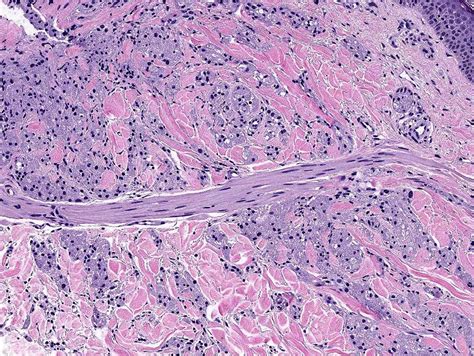

Histopathological Features

The histopathological features of granular cell tumours are distinctive and play a crucial role in their diagnosis. Key features include:

• Large, polygonal cells with abundant granular cytoplasm

• Small, centrally located nuclei

• Abundant lysosomes within the cytoplasm

• Positive staining for S-100 protein, a marker for neural and melanocytic differentiation

These features help differentiate GCTs from other types of tumours, such as rhabdomyomas and alveolar soft part sarcomas, which may have a similar appearance but different clinical behaviours.